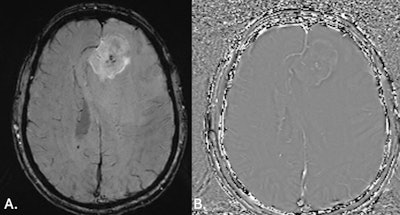

(A) MRI brain SWI axial scan shows left frontal lobe lesion with mass effect and blooming artefact representing microhemorrhages within the lesion (note that contrast was given to the patient prior to acquisition of SWI images). (B) MRI brain SWI phase images axial: haemorrhagic lesion shows a bright/positive shift on the phase image due to paramagnetic susceptibility effect. All figures courtesy of Dr. India Plath and Prof. Alan Coulthard, Department of Medical Imaging, Royal Brisbane and Women’s Hospital.